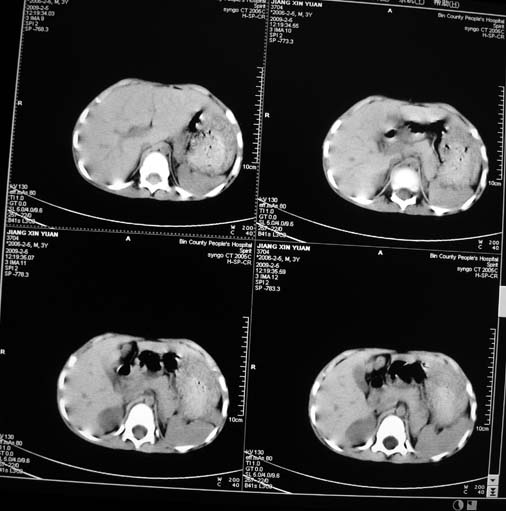

男,3岁,肾母细胞瘤术后,肝脏的低密度是什么?

胰尾下方见两枚囊形灶,肠管?病灶?左侧肾上腺区见团块状影,转移病灶?术后表现?建议与前片对比,肝脏病灶好像有牛眼表现,不除外转移,如果不增强,建议加做个b超,至少可分清其囊性或者实性,又便宜,免费自已给他弄一下也行,对诊断有帮助

左肾母细胞瘤术后,多发性转移可能性大。

左肾母细胞瘤术后:肝脏多发低密度灶,考虑转移可能性大。

左肾母细胞瘤术后:肝脏多发低密度灶,考虑转移可能.请结合临床及增强以及术前检查等